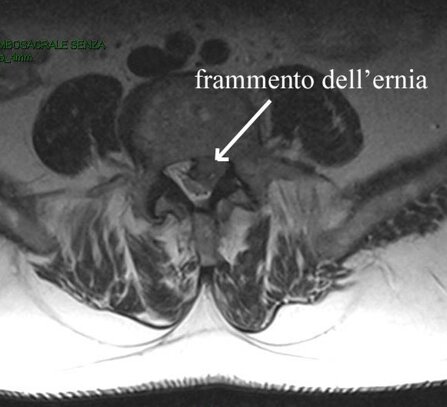

Persona affetta da 2 mesi da dolore lombare e sciatalgia sinistra persistente, molto intensa.

Una risonanza lombare evidenziava un’ernia discale molto voluminosa espulsa L5-S1 sinistra.

Non presentava disturbi di forza all’esame neurologico obbiettivo.

Il paziente non era incline al trattamento neurochirurgico e si optava per ozonoterapia.

Nel corso delle sedute (effettuate alcune con tecnica ecoguidata iuxtaradicolare L5-S1 ed altre paravertebrali) graduale regressione del mal di schiena e diminuzione el dolore sciatico.

Alla fine delle 6 sedute (3 settimane di trattamento), regressione completa del dolore allagamba sinistra, con possibilità di ripresa dell’attività lavorativa.